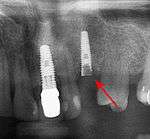

From these theoretical risks, derive the real world complications. Long-term failures are due to either loss of bone around the tooth and/or gingiva due to peri-implantitis or a mechanical failure of the implant. Because there is no dental enamel on an implant, it does not fail due to cavities like natural teeth. While large-scale, long-term studies are scarce, several systematic reviews estimate the long-term (five to ten years) survival of dental implants at 93–98 percent depending on their clinical use.[1][2][3] During initial development of implant retained teeth, all crowns were attached to the teeth with screws, but more recent advancements have allowed placement of crowns on the abutments with dental cement (akin to placing a crown on a tooth). This has created the potential for cement, that escapes from under the crown during cementation to get caught in the gingiva and create a peri-implantitis (see picture below). While the complication can occur, there does not appear to be any additional peri-implantitis in cement-retained crowns compared to screw-retained crowns overall.[40] In compound implants (two stage implants), between the actual implant and the superstructure (abutment) are gaps and cavities into which bacteria can penetrate from the oral cavity. Later these bacteria will return into the adjacent tissue and can cause periimplantitis. As prophylaxis these implant interior spaces should be sealed.[41]